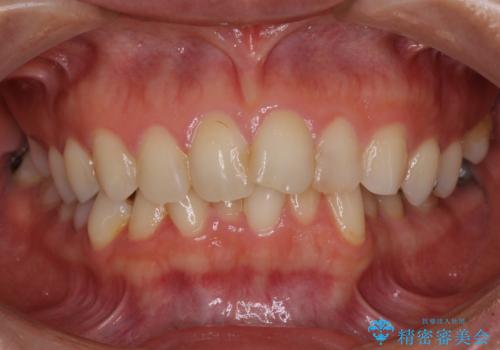

前歯の叢生をいつの間にか改善 インビザラインによる矯正治療

- 前歯のデコボコを気にして来院された患者様です。

IPR(歯と歯の間を削る)によってデコボコが解消するように設計し、インビザラインにより治療を行うこととしました。

下顎善の叢生をもう少し改善したかったのですが、患者様は十分に整ったとのことで治療を終えることになりました。